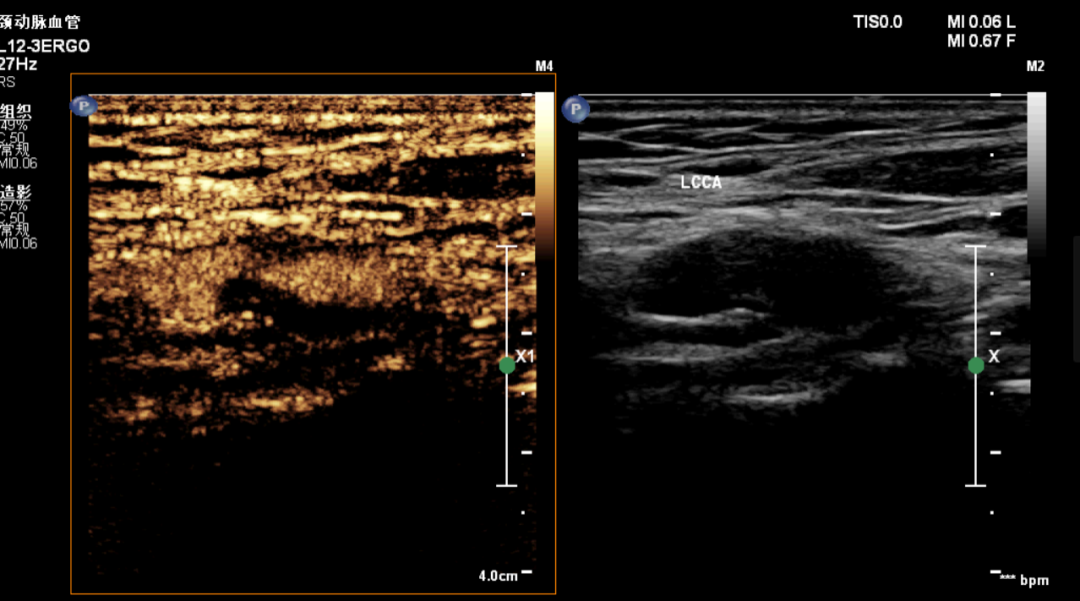

通过注射造影剂得到成大伯的超声造影,检查双幅对比图像,明确了颈动脉低回声斑块的边界并检测到其内的新生血管。

面对成大伯的各种疑惑,在超声医学科吴慧颖副主任和血管组组长李彤副教授的建议下,成大伯进行了颈动脉超声造影检查。检查中发现,成大伯的颈动脉虽然没有达到重度狭窄,但斑块内有一些的新生血管分布,属于不稳定斑块,存在破裂风险。临床医生根据超声检查等结果进行综合评估,建议成大伯暂时不做手术,但需要戒烟酒,服用他汀类药物来改善斑块稳定性,抑制斑块进展,从而减少脑卒中发生。